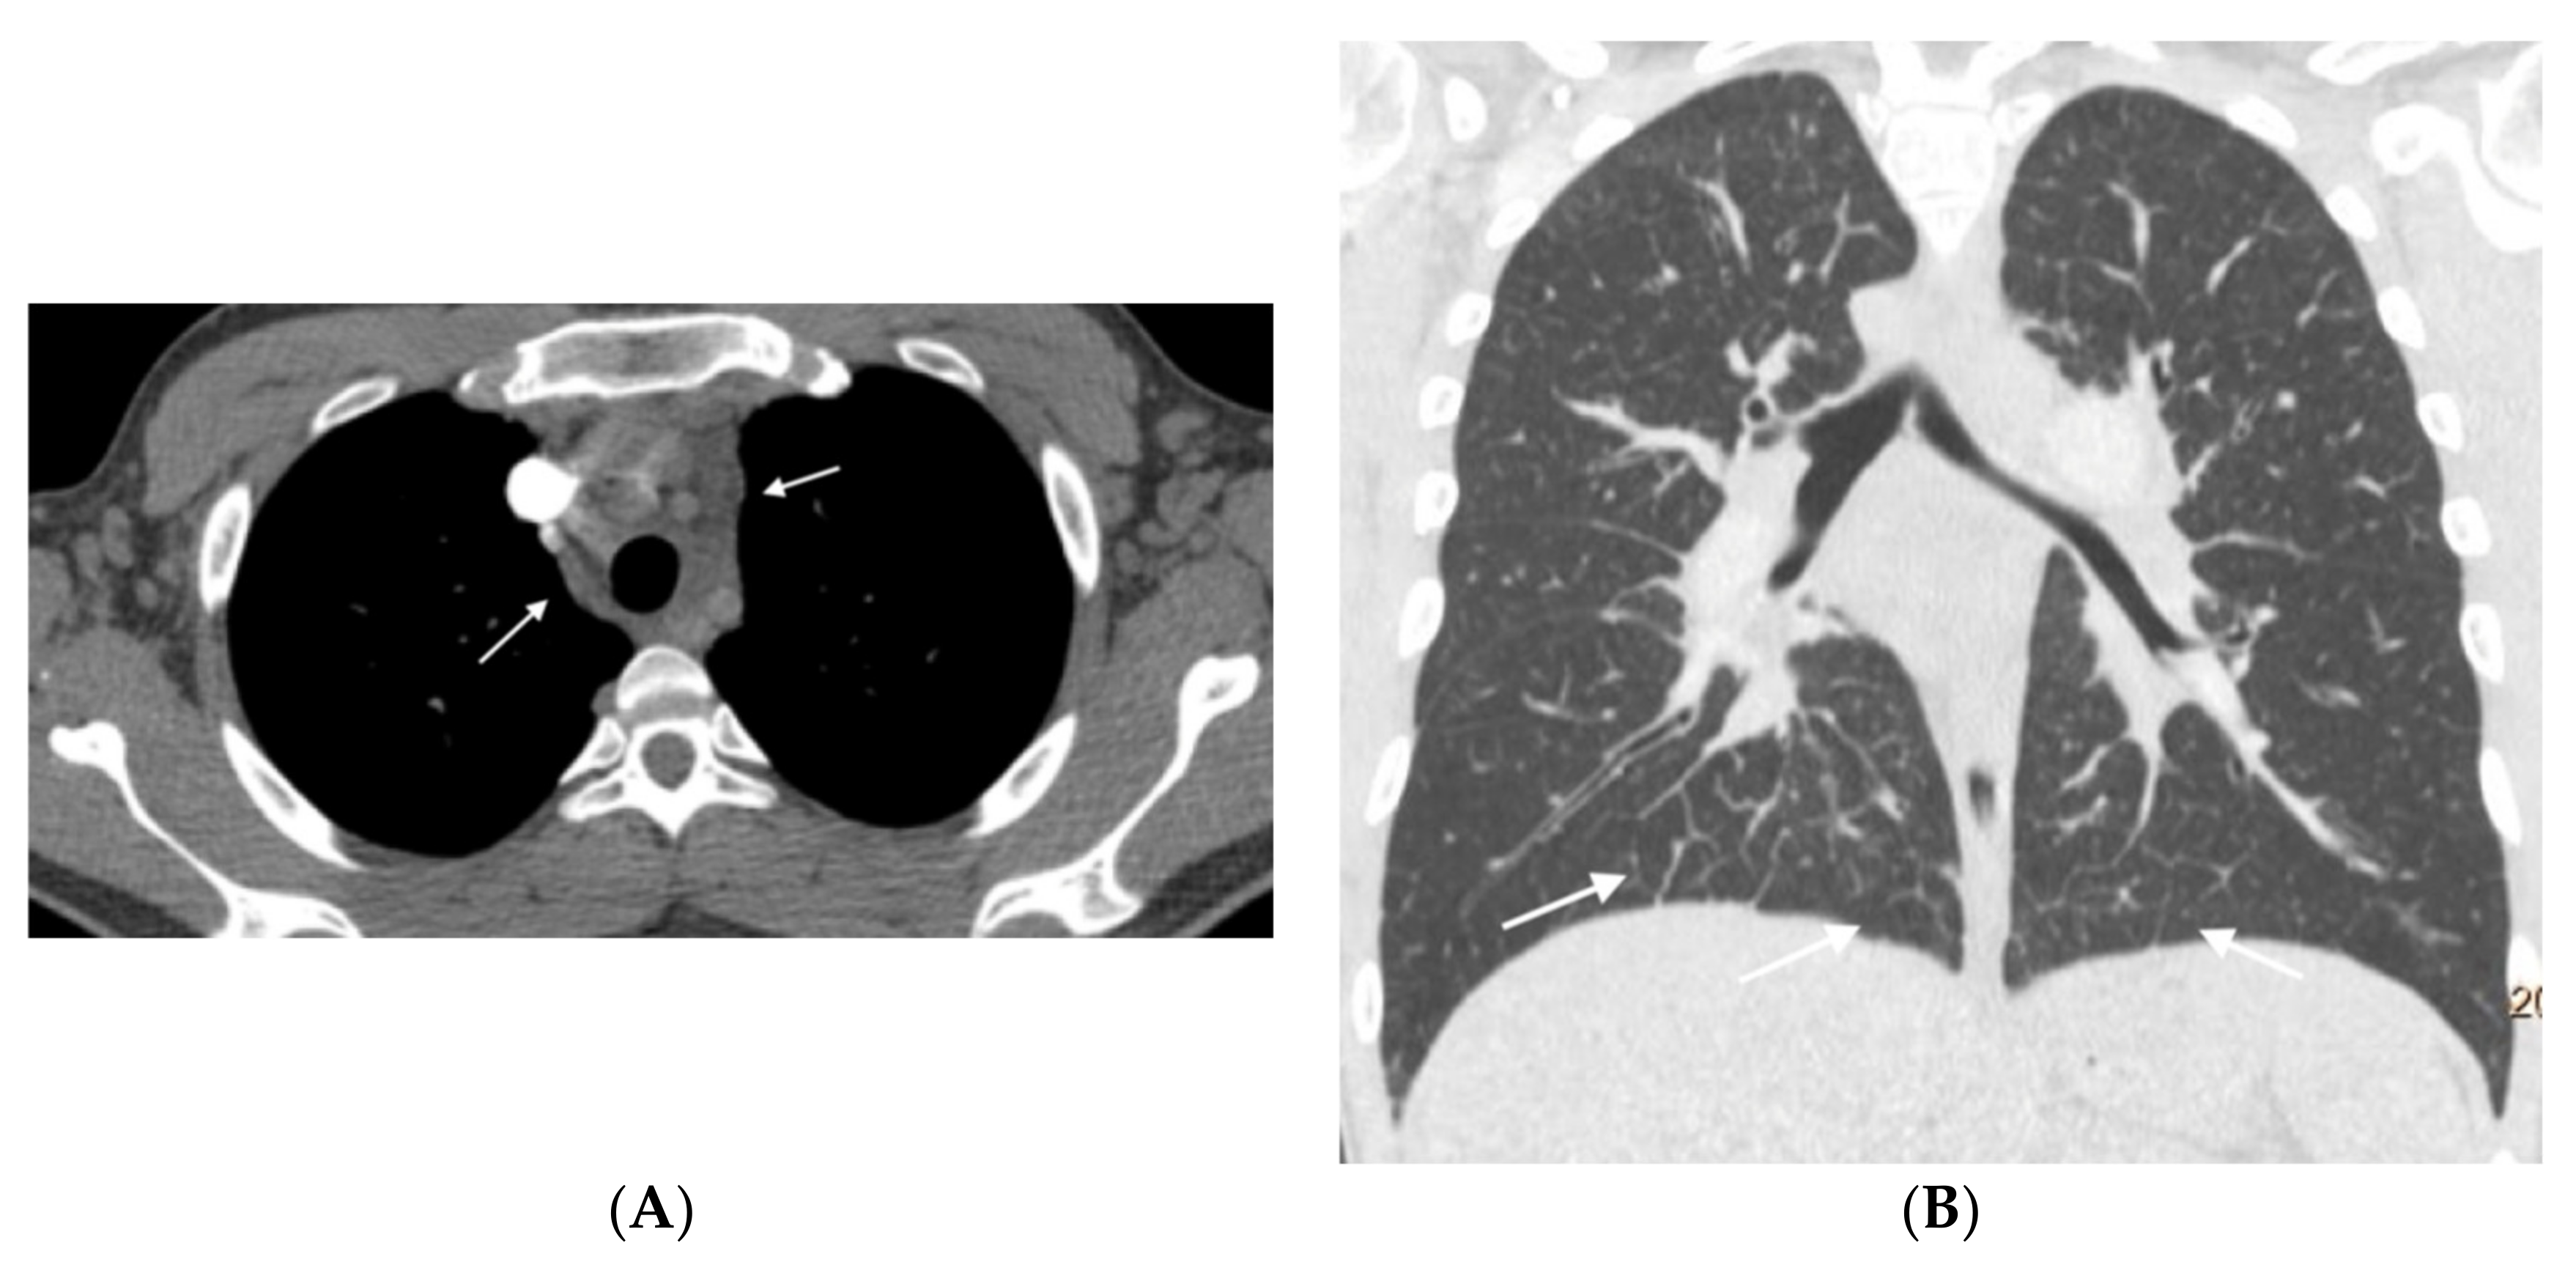

Figure 6.

Nineteen-year-old male with hereditary PVOD and two typical findings. (A) Prevascular and right paratracheal lymphadenopathy (arrows); (B) coronal image. Septal lines in both lower lobes (arrows). There is no ground glass parenchymal involvement.